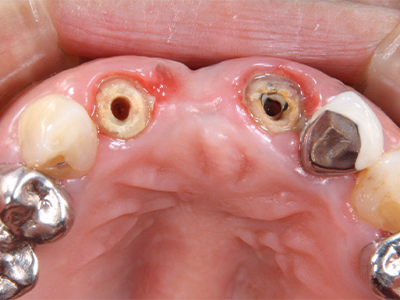

治療前

右下奥歯で咬むと違和感がある/歯ぐきが腫れてきた

治療内容

- ① 顕微鏡視下根管治療(マイクロエンド)

- ② 根管拡大・洗浄2回

- ③ 2ヶ月経過観察で再生反応確認後に根管充填

- ④ マイクロスコープ下でファイバーコア築造+セラミック冠装着

約3ヶ月半(1回の治療:1~2時間)

- マイクロエンド132,000円

- ファイバーコア 22,000円

- 仮歯 6,600円

- セラミック冠 165,000円

- 術後の腫れ・痛み・出血

- 慢性根尖性歯周炎が再発する可能性

- 定期的なチェックが必要

サイナストラクトは消失し、CTでも透過像の改善を確認。

術後数日で痛み消失し、セラミック装着後も良好な咀嚼が可能。

現在は年1 回の定期チェックを継続中。